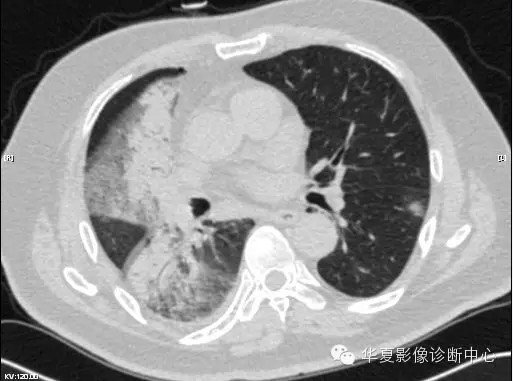

【病例学习】甲型H7N9禽流感一例

男性 63

发热咳嗽5天

2013-4-5拍片示右肺实变,收入院,追问病史,发病期间肌肉酸痛,头痛,无腹痛腹泻,无明显胸闷气急,无意识改变。有高血压病史,无其它病史。

2013-4-7CT进一步检查。

最终诊断:H7N9。